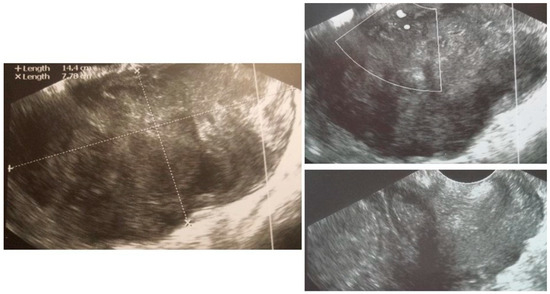

| 7 (29) | Atypical uterine lesion | Figure A7 | Yes | Yes | Leiomyoma (UG-TUC core needle biopsy) | Yes | Leiomyoma with signs of degenerations | Yes | Yes |

| 8 (52) | Atypical uterine lesion | Figure A8 | Yes | Yes | Total abdominal hysterectomy performed without core need biopsy, because of patients age and lesion ultrasound pattern recognition. Note: frozen section result: leiomyoma | Yes | STUMP | - | - |